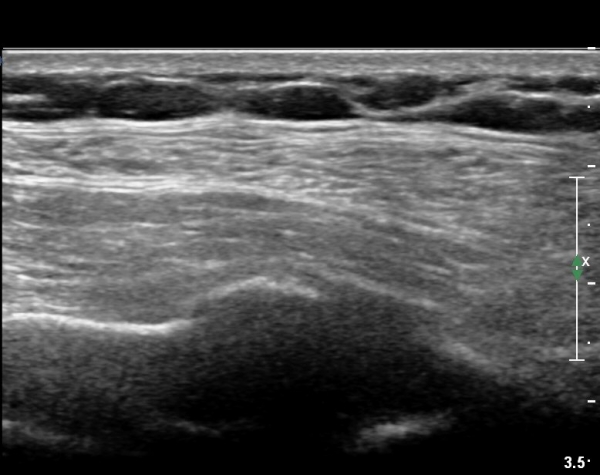

on moving of prove a little, there is bony protrusion(osteoblastic lesion) and hypoechoic(osteolytic)  lesion(image 2, 3, 4).

in transverse scan, visualization of osteoblastic mass with central osteolytic lesion(image 5, 6).

As like this case, visualization of osteoblastic lesion and osteolytic lesion in simultaneously  suggests a malignant mass.